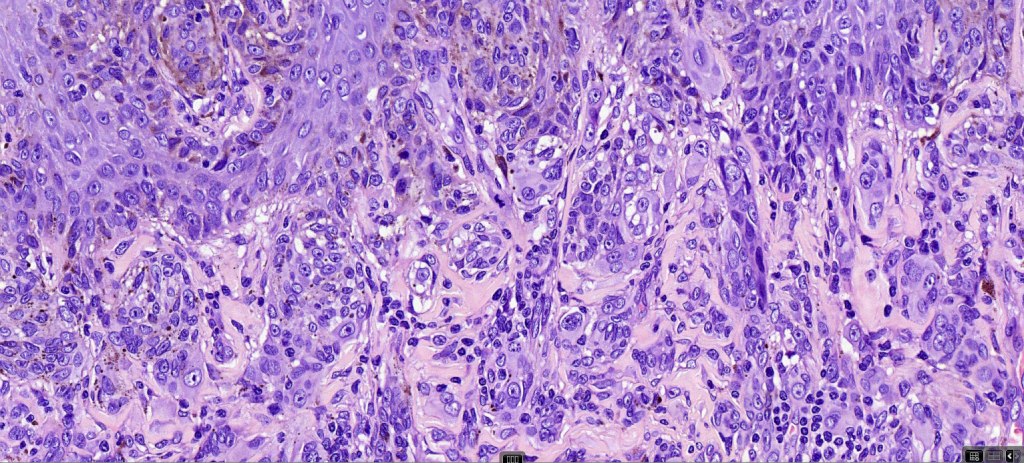

Combined Spitz & common blue nevus